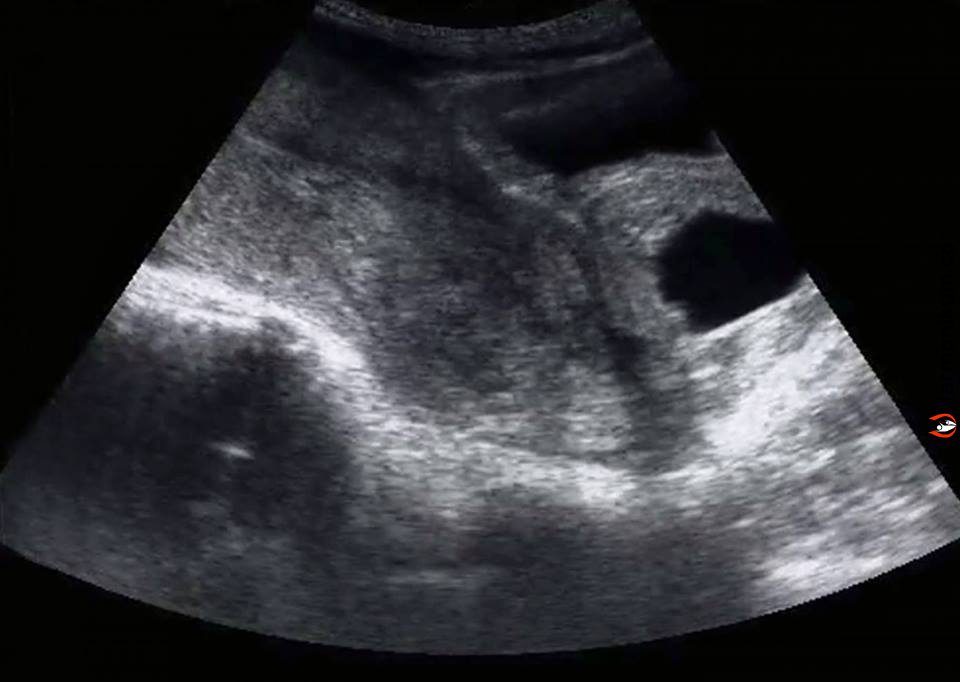

De ezek a képek mások voltak, nem olyanok mint amit barátaim feltettek a Facebook-ra. Valami nagyon nem volt rendben. Nem is láttam már semmit, testem néhány órával később készen állt arra, hogy kidobja a magzatot.

A nővérke csendben volt. Kiment a szobából a férjem pedig odajött hozzám, hogy megnyugtasson. Nem kellett nekem mondani, hogy minden rendben mert már rengeteg ultrahang felvételt láttam az Instagram-mon is. Tudtam, hogyan kellett volna most kinéznie a felvételen egy 8 hetes magzatnak.